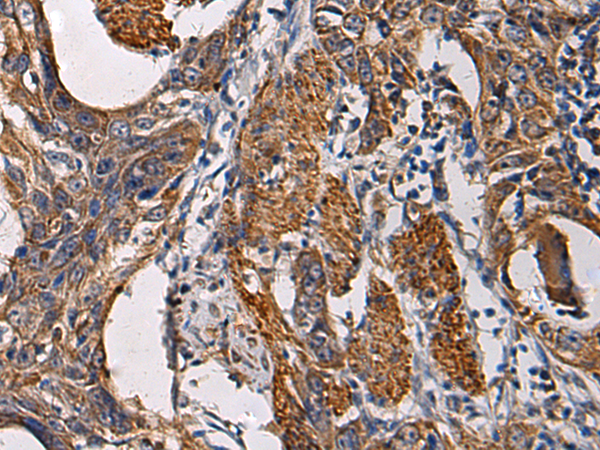

IHC positive control: |

Human esophagus cancer and Human breast cancer |